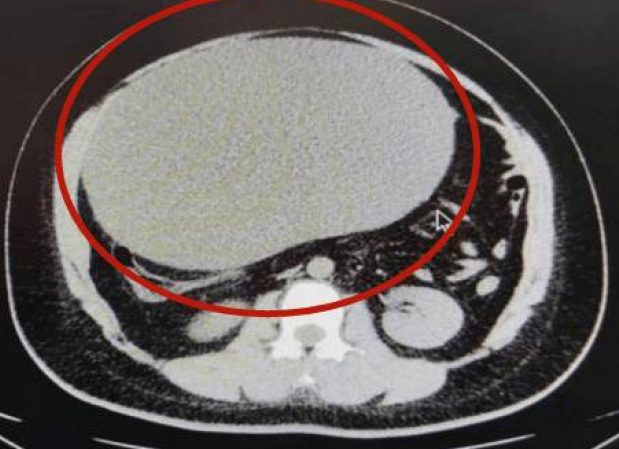

经CT检查显示,这名患者腹部有一个巨大的卵巢囊肿,手术切除后重达8公斤,相当于三胞胎的重量,比一个足球还大。医师还透露,女患者囊肿的囊液取出来,也大概有5000毫升,相当惊人。